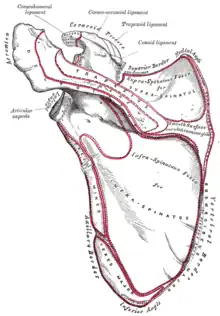

Costal surface of left scapula. Suprascapular notch shown in red. | |

Costal surface of left scapula. Suprascapular notch visible in the red square. | |

Left scapula. Suprascapular notch shown in red.

Left scapula. Suprascapular notch shown in red. Animation. Suprascapular notch shown in red.

Animation. Suprascapular notch shown in red. Left scapula. Dorsal surface. (Sup. notch visible at top center.)

Left scapula. Dorsal surface. (Sup. notch visible at top center.) Costal surface of left scapula. Suprascapular notch labeled at top center.

Costal surface of left scapula. Suprascapular notch labeled at top center.